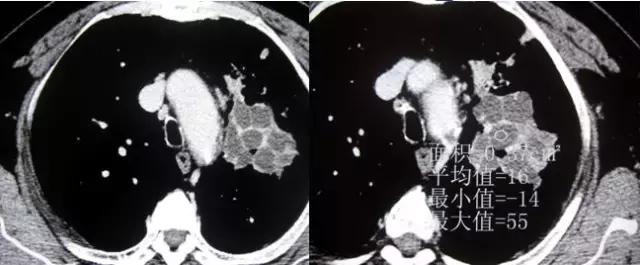

CT征象六:空洞与空腔

空洞(cavity)是肺内病变坏死液化,经引流支气管排除及气体进入而形成的透亮区。

空腔(aircontaining space)是肺内正常生理腔隙的病理性扩大。

空洞(cavity)分型 :

虫蚀样空洞(无壁空洞)

薄壁空洞(≤3mm)

厚壁空洞(>3mm)

疾病:大叶干酪性肺炎

疾病:继发型肺结核

结核球厚壁空洞

肺脓肿厚壁空洞

肺鳞癌厚壁空洞